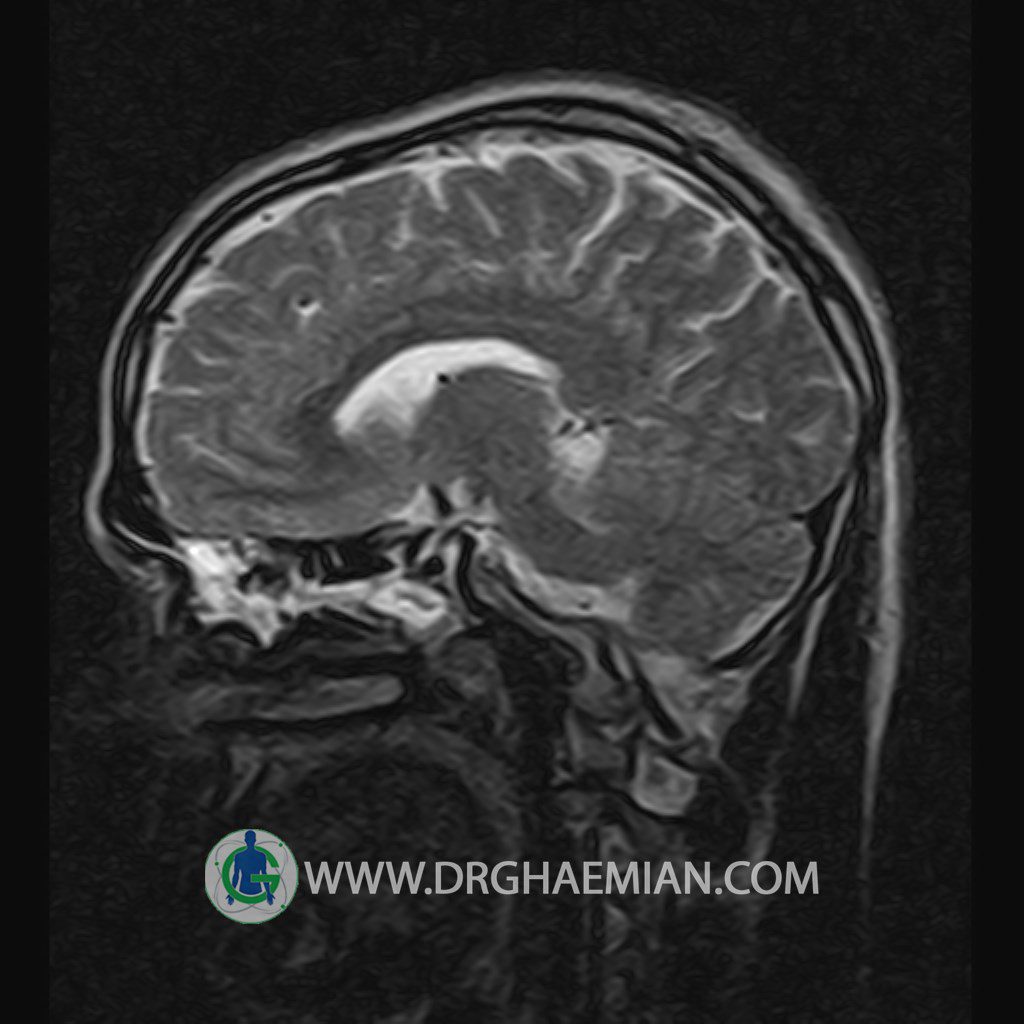

پزشکان اغلب از تصویربرداری ام آر آی برای تشخیص و درمان عارضه های پزشکی که فقط با استفاده از اشعه ایکس یا میدان مغناطیسی و امواج رادیویی قابل مشاهده است، استفاده می کنند. دستگاه ام آر آی تصاویر دقیق از ساختار های داخلی بدن ایجاد می کند. در این کیس یک میکروآدنوم در هیپوفیز بیمار مشاهده می شود.

HYPOPHYSIS MRI

(with and without contrast)

Technique: Axial , coronal T1 , Axial , coronal , sagittal T2 , Axial, coronal T1 post Gd & 64 dynamic thin coronal slices.

REPORT :

The infundibulum is centered and of normal size .

The optic chiasm and suprasellar spaces appear normal .

– Small hypoenhancing mass lesion ( 3 x 4 mm ) in posterior of pituitary stalk suggestive for micro adenoma

– Mucosal thickening in ethmoid & maxillary sinuses

is seen